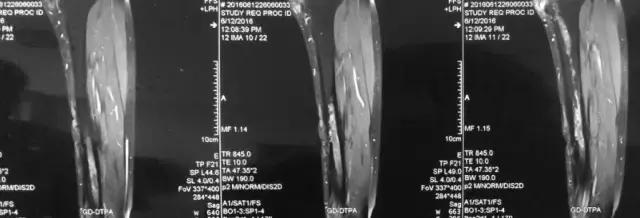

影像检查

诊断:感染。 检查:膝关节MRI,确认伤口窦道是否与髓腔相通。 治疗:1、血沉和C反应蛋白正常,目前无需特殊处理。 2、如果窦道反复出现或血沉和C反应蛋白升高可考虑手术。如证明窦道与髓腔相通,需行扩髓。

核磁示中下段骨髓炎,上面切口处流脓,请问张主任你的意见要上手术吗?